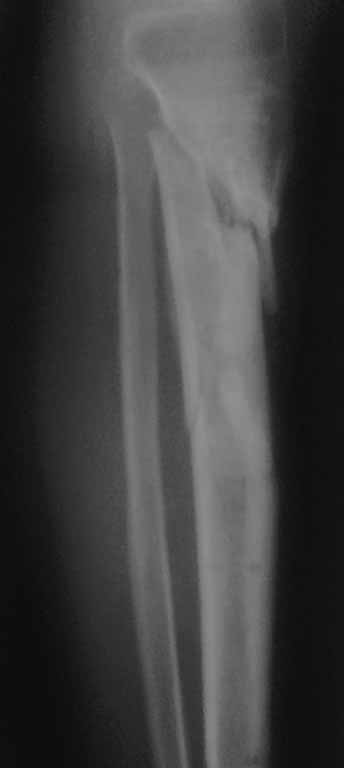

Важны мнения опытных докторов владеющих интрамедуллярным остеосинтезом. Пациент 50 лет.В анамнезе з/оскольч.перелом в/з-с/3 б/б кости. Был в АВФ 9 мес, демонтирован по его словам по поводу спицевой инфекции.также был со слов вскрыт гнойник на передней поверхности голени в зоне ложняка. на данный момент клинически: патол.подвижность в в/з голени и заживающая рана 0,2*4см по передней поверхности голени в зоне ложняка с скудно-умеренным серозным отделяемым( скорее вне зоны проведения спиц). Подвижность -умереннная. Трофических и сосудистых нарушений можно сказать нет. Сгибание в коленном суставе возможно без насилия ок. 50град. Вопрос - как делать? Нам предстваляется два пути: 1.Не дожидаясь заживления раны о/с АВФ,с открыванием ложняка: почистить его+ остеотомия малобрецовой ближе к н/3-с/3 границе. 2.перевязывать рану, после заживления подождать недельки две. Паралельно разрешить приступать на конечность. 2.1Если гной будет то см.вариант1.

Жаль, что нет фасной проекции. Перелом на 2 уровнях, есть искривление костно-мозгового канала. Проксимальный отломок короткий. Вывод: лучше не штифтовать.

3.Перелом на 2 уровнях, есть искривление костно-мозгового канала. Проксимальный отломок короткий.

Ни одного снимка, где было бы видно коленный сустав.. Не совсем понимаю столь яростное отрицание стержня, проксимальный отломок не так уж и короток, 3 разнонаправленных винта войти смогут. Учитывая продление на диафиз, если выбирать между здоровенной пластиной и стержнем, ИМХО целесообразнее стержень.